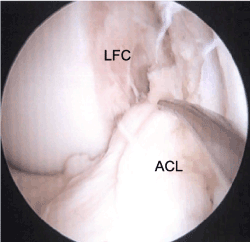

The patient is a skeletally mature 17-year-old female that presented with right knee pain after a non-contact cutting injury sustained while playing soccer. An MRI of the right knee revealed a complete ACL tear that appeared to be a proximal avulsion, without other concomitant intra- or extra-articular pathology (Figure 1). Intra-operative evaluation confirmed the femoral-sided avulsion of the ACL (Figure 2). The ligament tissue quality was robust and had the appropriate length and excursion to be reapproximated to the femoral footprint without laxity or undue tension, so it was determined that this tear was amenable to repair. The repair was performed by passing two No. 2 non-absorbable sutures through the proximal ACL stump in luggage-tag fashion, one in the anteromedial bundle, and the other through the posterolateral bundle. These suture ends were then passed through two transosseous tunnels made in their respective bundle attachments of the femoral footprint, exiting the lateral femoral cortex. The repair sutures were fixed on the femoral side with a Hewson Ligament Button (Smith and Nephew) on the lateral cortex. This repair was augmented with a singular 2mm FiberTape (Arthrex, Inc), fixed through separate femoral and tibial tunnels with a PushLock anchor on the femoral side, and a SwiveLock anchor on the tibial anterior cortex (Arthrex, Inc). The ACL was found to have appropriate tension throughout range of motion and post-fixation exam demonstrated excellent stability to Lachman and pivot shift tests (Figure 3).

Figure 2. Arthroscopic view from the anterolateral portal viewing into the notch, demonstrating the avulsion of the ACL from the femoral footprint on the lateral femoral condyle. The probe is demonstrating the ligament displacement from its femoral insertion. (ACL = anterior cruciate ligament; LFC = lateral femoral condyle)